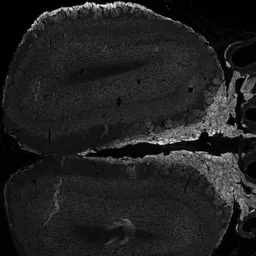

IHC-Fr analysis of PFA-perfused mouse Olfactory bulb using GTX89311 NCAM2 antibody, C-term.

Red : NCAM2

Blue : VGLUT2

Green : NQO1

Antigen retrieval : citrate buffer pH 6 at 95ºC for 10min

Dilution : 0.5μg/ml